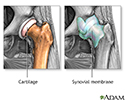

Osteoarthritis vs. rheumatoid arthritis - illustration

Osteoarthritis vs. rheumatoid arthritis

illustration